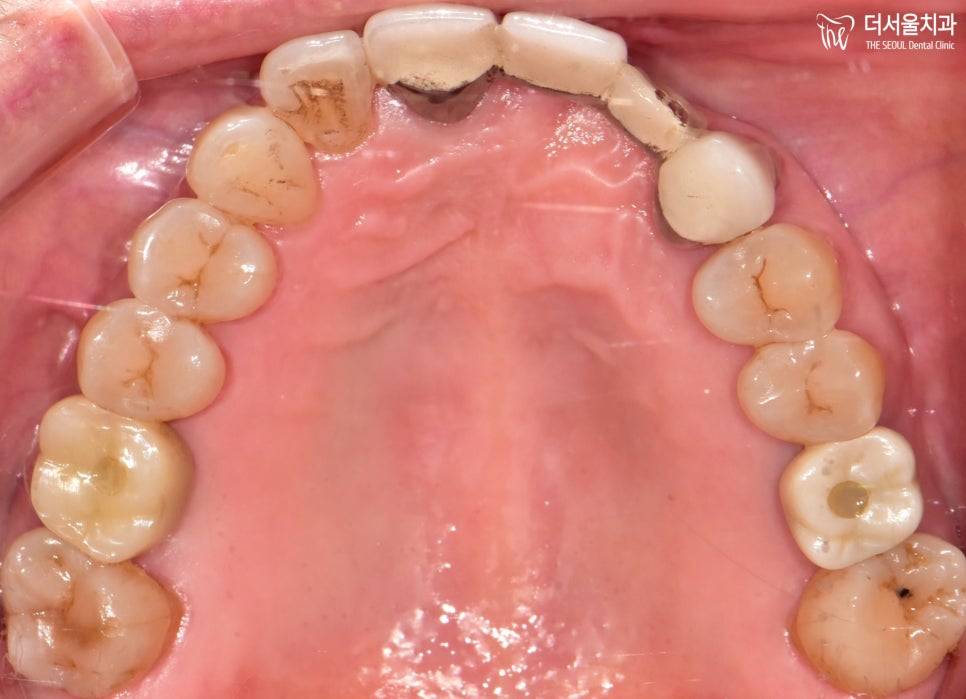

그 후, 튼튼히 결합이 이뤄진 뒤에

크라운을 세팅하여 수술은 잘 끝마쳤습니다.

양쪽 임플란트 식립은

크게 티가 나지 않게 잘 해결되었죠?

환자분 또한 없던 어금니가 생겨서

잘 맞물리는게 너무 좋다고 그러셨는데요.